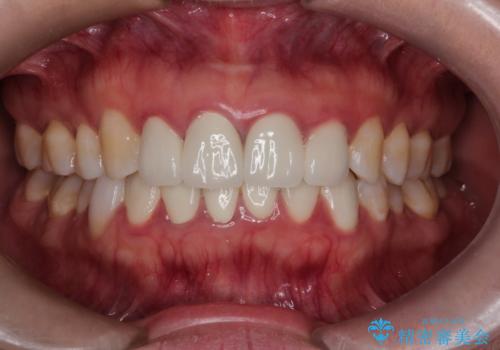

【オールセラミック】下の前歯が痛い。

- 以前に治療した前歯が痛むことを主訴に来院されました。

根っこに病気があり、根管治療から被せ物まで治療を行いました。

根管治療を行った後、3ヶ月間治癒の確認をしてからオールセラミックスペシャルで治療を行いました。